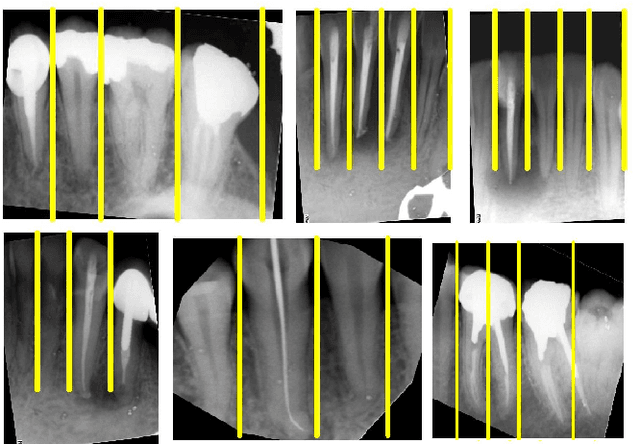

Abstract:Image processing techniques has been widely used in dental researches such as human identification and forensic dentistry, teeth numbering, dental carries detection and periodontal disease analysis. One of the most challenging parts in dental imaging is teeth segmentation and how to separate them from each other. In this paper, an automated method for teeth segmentation of Periapical dental x-ray images which contain at least one root-canalled tooth is proposed. The result of this approach can be used as an initial step in bone lesion detection. The proposed algorithm is made of two stages. The first stage is pre-processing. The second and main part of this algorithm calculated rotation degree and uses the integral projection method for tooth isolation. Experimental results show that this algorithm is robust and achieves high accuracy.